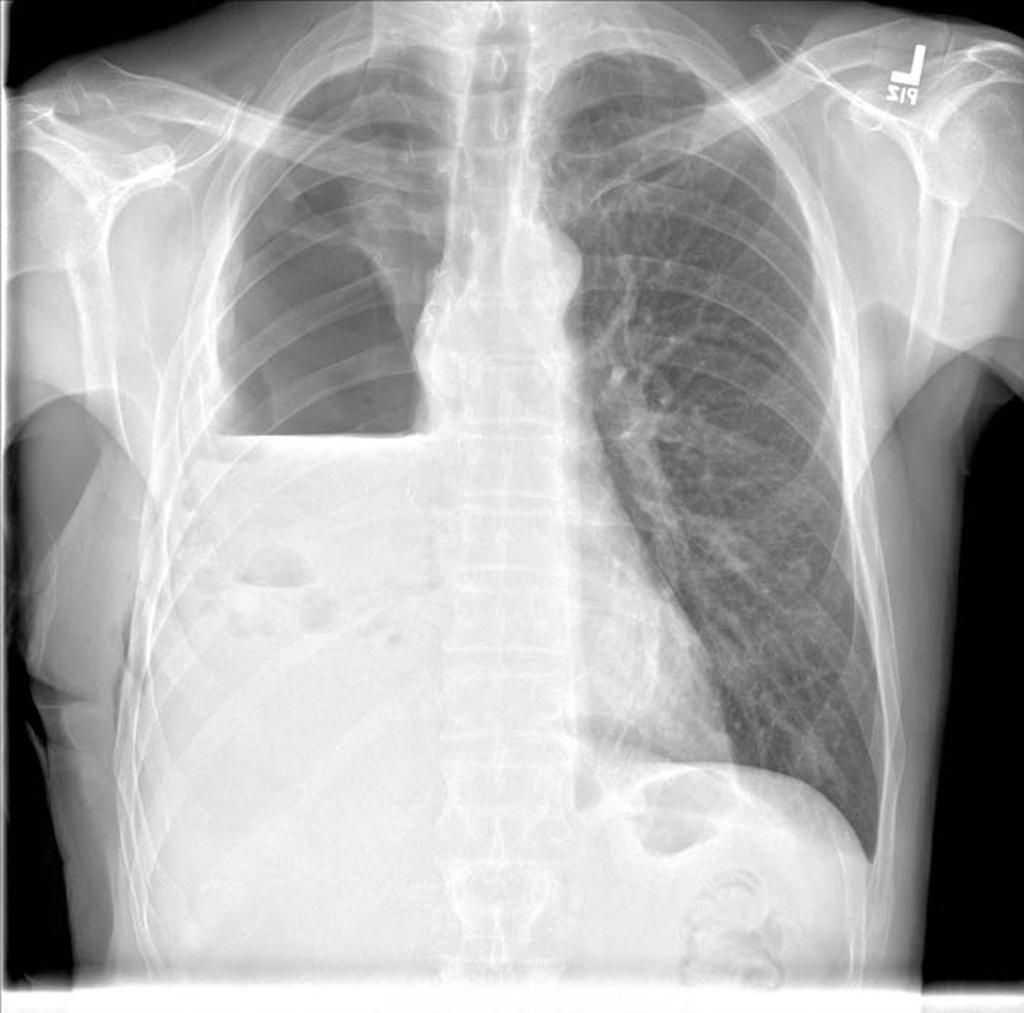

Left Atrial Enlargment